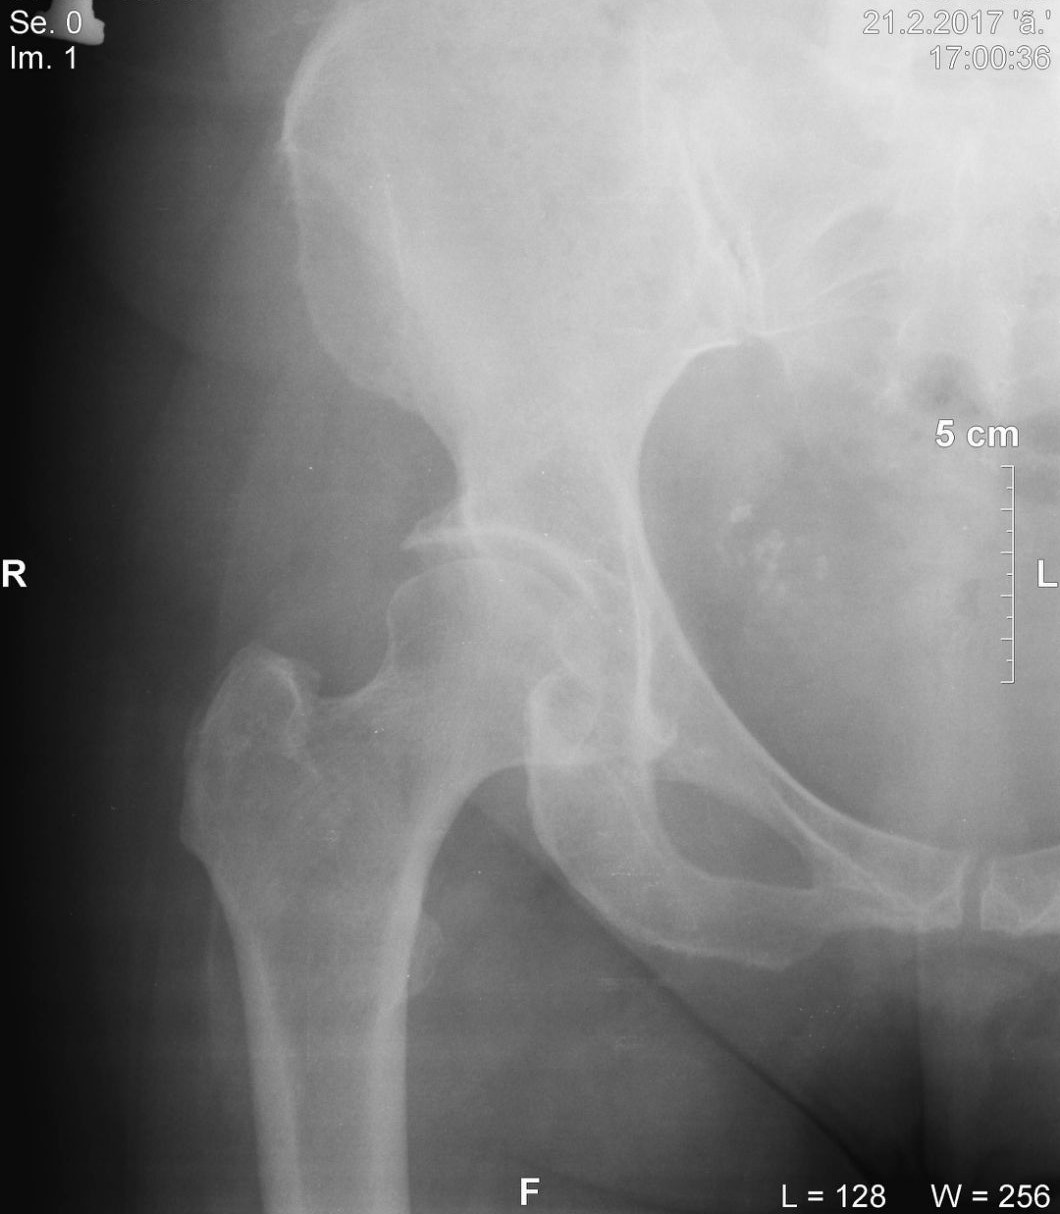

Здравейте,майка ми е на 60 години.От 5-6 месеца изпитва болка отпред в дясното бедро .Отиде на преглед при невролог,направиха й рентгенова снимка и й поставиха диагноза периставна остеоартроза 3 степен. Само с тази снимка може ли да се каже,че това е окончателната диагноза,трябва ли да се правят други изследвания. Лечението е с Дипрофос,Мовалис и болкоуспокояващи. За напред трябва ли да спазва хранителен режим,да приема хранителни добавки или нещо друго за подобряване на състоянието .Благодаря предварително !!!

media-share-0-02-05-217b1fd573bd46a06337e570d237a953808bd418a5740f76fc9db7c9b8359289-875ba049-767f-41f0-baa4-6b1320821eef (4).jpg

Рентгенова снимка на бедрена става

media-share-0-02-05-217b1fd573bd46a06337e570d237a953808bd418a5740f76fc9db7c9b8359289-875ba049-767f-41f0-baa4-6b1320821eef (4).jpg (161.53 KiB) Прегледано 2378 пъти

Диагнозата е периставна остеослероза 3 степен,сбъркала съм по-горе !!!